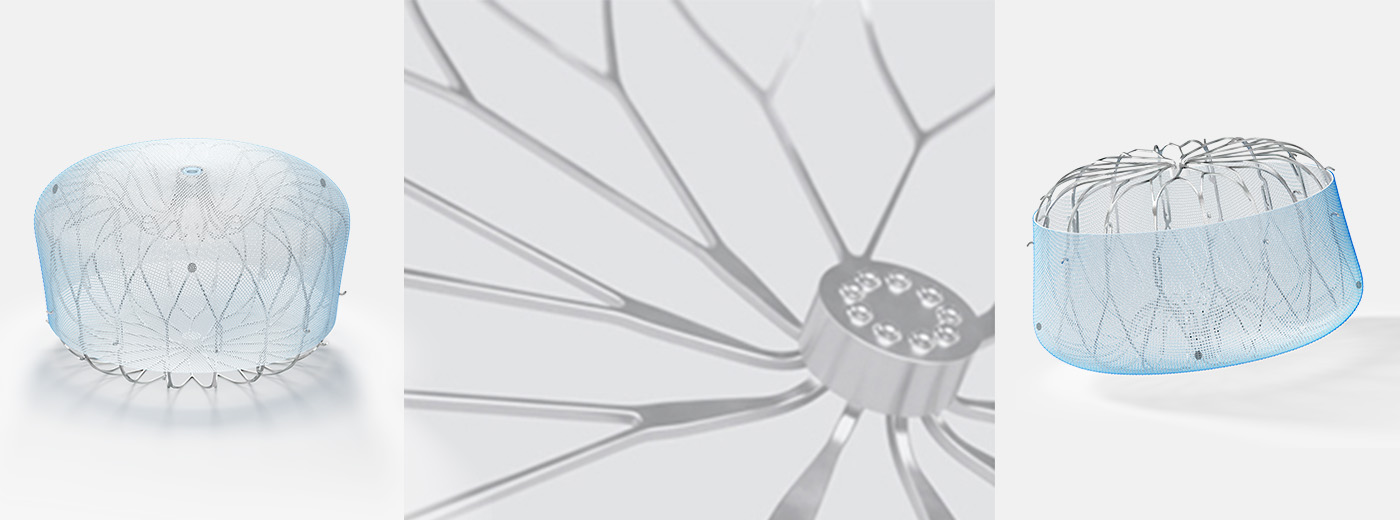

WATCHMAN FLX™ Pro LAAC Device

WATCHMAN FLX™ Pro is a Left Atrial Appendage Closure (LAAC) device, designed to reduce the risk of stroke in patients with non-valvular AF. Built on the proven performance of the WATCHMAN FLX™ device, the WATCHMAN FLX™ Pro device is optimized for healing.

WATCHMAN FLX™ LAAC Device

Learn about left atrial appendage closure (LAAC) procedure with WATCHMAN FLX™ and how it can help manage the risk of stroke for your patients with non-valvular AF.